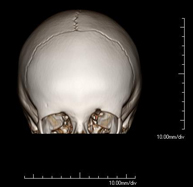

- TC Cráneo

Prueba radiológica que consiste en obtener imágenes del cráneo de alta definición anatómica (tronco cerebral, cerebelo, cerebro, calota craneal, etc.), mediante el empleo de un equipo de TC (Tomografía Computarizada).Indicaciones: traumatismos, cefalea, trastornos de la memoria, pérdida de fuerza súbita en una extremidad o mitad del cuerpo.